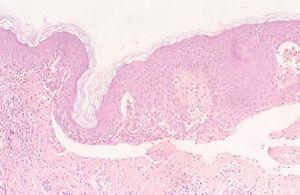

Varón de 79 años, monorreno, con hipertensión arterial en tratamiento con nifedipino e hipertrofia prostática benigna en tratamiento con doxazosina. Presentaba psoriasis de 12 años de evolución con empeoramiento progresivo de las lesiones que no se controlaban con tratamiento tópico. En abril de 2004 inició tratamiento con fototerapia UVB de banda estrecha (TL01) sin mejoría tras mes y medio de tratamiento, por lo que se sustituyó por tratamiento con PUVA. Entre la sexta-octava sesión comenzó a desarrollar lesiones ampollosas con intenso prurito en tronco, extremidades superiores y, de forma más aislada en extremidades inferiores en piel no afecta y sobre las propias lesiones psoriásicas (fig. 3), procediéndose a la suspensión del tratamiento. El estudio de hematoxilina-eosina (H-E) de la biopsia de una lesión ampollosa que se tomó fue compatible con el diagnóstico de penfigoide ampolloso (fig. 4). El estudio de inmunofluorescencia directa objetivó presencia lineal en membrana basal epidérmica de C3 y depósitos irregulares de IgM e IgA, con ausencia de complejos de IgG. La inmunofluorescencia indirecta demostró anticuerpos antimembrana basal epidérmica a título de 1/1.280, anticuerpos antisustancia intercelular epidérmica negativos.

Fig. 4.--Hematoxilina-eosina: vesícula subepidérmica con eosinófilos en su interior.